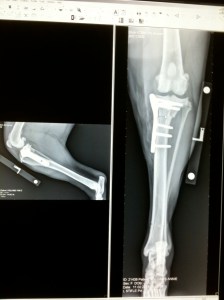

A TPLO, although now routine, has a pretty lengthy recovery period. After all, it entails cutting away a chunk of the tibia to prevent the femur sliding down it when the dog puts weight on its knee. So darling Annie had six weeks crate rest, which for a young and active dog is pretty hard going. It was far from easy for us too as she woke us every three hours during the night because she was hurting, or because she had an itch she couldn’t scratch or was downright miserable. But we got through it because in our book, there just was no alternative.

Months later, with the crate returned and the buster collar consigned to the loft we were woken in the night by the most terrible howling. The emergency vet diagnosed a fit and it wasn’t until later that day that we spotted the real cause of her distress, a small deep wound on her inner thigh. Somehow, Annie had punctured the muscle around the metal plate that was holding her leg together. The pain must have been unbearable for this stoical little dog to be so consumed by it.

The wound healed and then a few weeks later opened up again. For months we agonised over whether to take the now redundant plate out. Although the surgeon confirmed that she no longer needed it, we were concerned about yet another anaesthetic. Months went by with not a single incident and we started to relax and think that finally the area had built up enough scar tissue to protect the skin from knocks. But then, out of the blue it opened up again, but in two places this time. They were small, superficial wounds and aside from licking them, they didn’t seem to bother her, but they certainly bothered us.

Leaving a dog at the vets for an operation is never much fun. Leaving a dog so nervous she’s shaking from temple to tail is no fun at all. So imagine the fury when we get a call from the vet to say that after opening her up, he was unable to take the plate out because the original surgeon put two different types of screw into the leg but only told him about one.

Poor Annie was stitched up and sent home only to have to return two days later to have it done all over again, but this time with the benefit of two specialist screwdriver heads instead of the one.